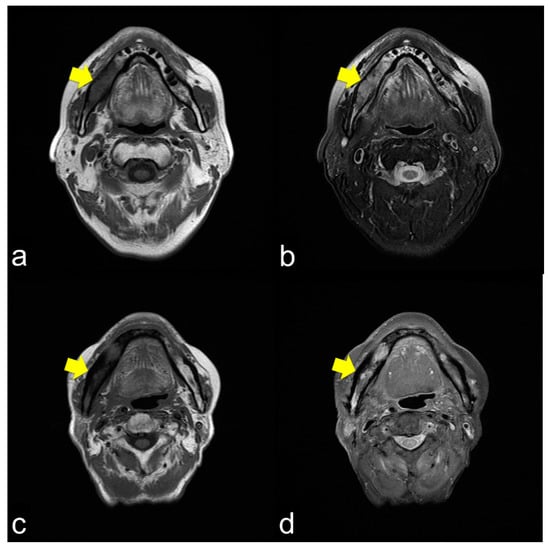

Figure 1.

Pre-treatment mandible on axial computed tomography (CT) scan (a) and osteoradionecrosis (ORN) mandible on axial CT scan (b). The image shows bony sclerotic changes with ORN (b) involving the right mandible compared to the pre-treatment mandible in the same lesion without periosteum reaction (arrowhead). These reactions may have been induced by irradiation.

All 42 (100%) patients showed T1 WI hypo-intensity in the symptom region (Figure 2a,c,e). In contrast, the T2 WI showed various aspects. Thirty (71.4%) patients with T2 WIs showed homogeneous hyper-intensity (Figure 2b), which showed a relatively mild inflammatory condition of bone marrow clinically. Heterogeneous hyperintensity was observed in 11 (26.2%) patients (Figure 2d). One patient (2.4%) showed homogeneous hypointensity (Figure 2f).

Figure 2.

(a) Axial T1-weight image (T1 WI) shows low signal intensity from the molar lesion to the ramus on right side of the mandible (arrowhead); (b) Axial T2-weight image (T2 WI) reveals high signal intensity on the right side of the mandible (arrowhead). The margins between the normal and abnormal bone marrow are not distinct. This condition usually shows mild inflammation of the ORN; (c) Axial T1 WI shows low signal intensity from the molar lesion to the ramus on the right side of the mandible (arrowhead); (d) Axial T2 WI reveals heterogeneous intensity on the right side of the mandible (arrowhead). The margins between the normal and abnormal bone marrow are not distinct. This condition usually results in severe ORN inflammation; (e) Axial T1 WI shows low signal intensity from the molar lesion to the ramus on the right side of the mandible (arrowhead); (f) Axial T2 WI reveals low signal intensity on the right side of the mandible (arrowhead). The margins between the normal and abnormal bone marrow are not distinct. This condition is bone necrosis, which shows less inflammation.